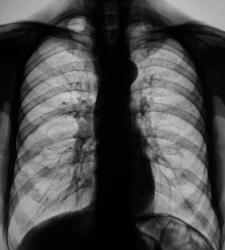

Смею предположить:в S1,2 слева усиление и деформация легочного рисунка за счет периваскулярной (перибронхиальной?) инфильтрации и участков пневмосклероза плевро- костальные наложения?), на этом фоне определяется( по крайней мере одно по поводу интенсивности ) дополнительное округлое образование средней интенсивности с инфильтрацией легочной ткани вокруг. Мне кажется больше данных за активный процесс.

На мой взгляд также процесс имеет "активность" с учётом наличия очагов средней интенсивности

инфильтративный туберкулёз в активной фазе.